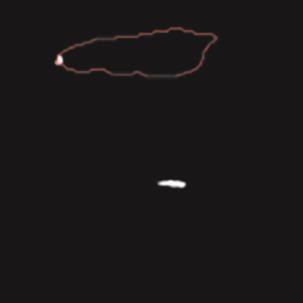

乳腺癌是全球女性最常见的恶性肿瘤之一,准确的病变分割对于乳腺癌的早期诊断与治疗具有重要意义。然而,由于病变形态的多样性以及超声成像机制的复杂性,现有基于深度学习的乳腺超声图像病变分割方法在分割准确性方面仍面临巨大挑战。为进一步提升乳腺超声图像中病变区域的分割精度,该文基于经典U-Net架构,提出了一种新型乳腺超声图像病变分割网络(CWSASKM-BBAM-Net)。首先,在网络中引入逐通道空间自适应选择核卷积模块(CWSASKM),根据不同通道的语义特征为每个空间位置自适应选择感受野大小,以增强多尺度信息的建模能力;然后,引入双向边界感知机制(BBAM),通过融合正向与反向注意力,对目标显著区域及其边界进行协同建模,同时逐步提升对非显著区域与病变区域的区分能力,以进一步强化边界信息的表达;最后,在3组公开乳腺超声图像数据集(BUSI、UDIAT和STU)上开展分割实验。结果表明:该方法在数据集BUSI上的杰卡德指数、精确率、召回率和Dice相似系数分别为71.97%、82.85%、81.40%和80.44%,较次优方法分别提升1.69、1.05、1.28和1.84个百分点;在数据集UDIAT上,这4项指标分别达到78.14%、88.31%、86.73%和86.10%,较次优方法分别提升了2.75、2.04、0.56和2.01个百分点;在外部数据集STU上,该方法也取得了优于其他方法的整体表现。实验结果表明,CWSASKM-BBAM-Net在乳腺超声图像分割任务中展现出更优的整体性能。